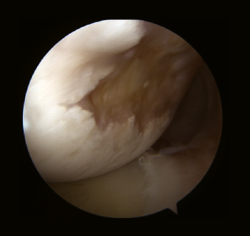

Burkhart y De Beer(19,20) enfatizaron el papel de la artroscopia como herramienta para el diagnóstico dinámico y definitivo de las lesiones “no enganchantes y enganchantes”, y la falta de una correcta interpretación de los defectos óseos era la causa de muchos fracasos en la reparación primaria de una IGH por error en la técnica quirúrgica adecuada.

Las mediciones on-track y off-track son valores comparables a los conceptos de “lesión no enganchante o enganchante” de Burkart et al.(19), la diferencia es que las primeras se miden con una 3D-TAC antes de la cirugía, permitiendo establecer la indicación de la técnica quirúrgica más apropiada antes de la cirugía (reparación de partes blandas vs. tope óseo), y la valoración de las lesiones “no enganchantes o enganchantes” se realiza artroscópicamente (Figuras 5 y 6).

Figura 6. Lesión de Hill-Sachs off-track/enganchante.